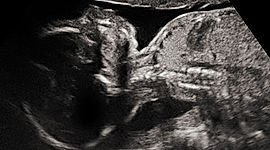

V poradně pro těhotné absolvuje žena několik různých doporučených vyšetření, která sledují její zdravotní stav a kondici a vývoj plodu.

V několika přesně určených termínech podstupuje těhotná žena i další než jen pravidelná vyšetření. Sleduje se zejména stav a kondice plodu, ale i riziko komplikací u matek, jako je například těhotenská cukrovka či preeklampsie.

Narození dítěte se závažnou vrozenou vývojovou vadou patří mezi nejzávažnější rodinné tragédie. Proto je ženám během těhotenství nabízeno vyšetření, které může vrozené poruchy plodu odhalit. Nejčastější geneticky podmíněnou poruchou je Downův syndrom.